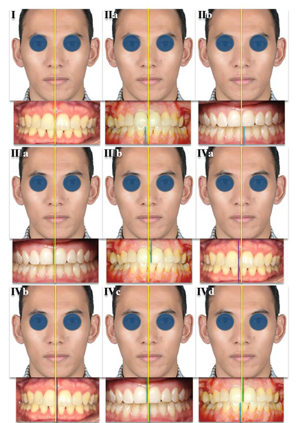

Vincenzo Ronsivalle, Federica Casella, Grazia Fichera, Orazio Bennici, Cristina Conforte and Antonino Lo Giudice